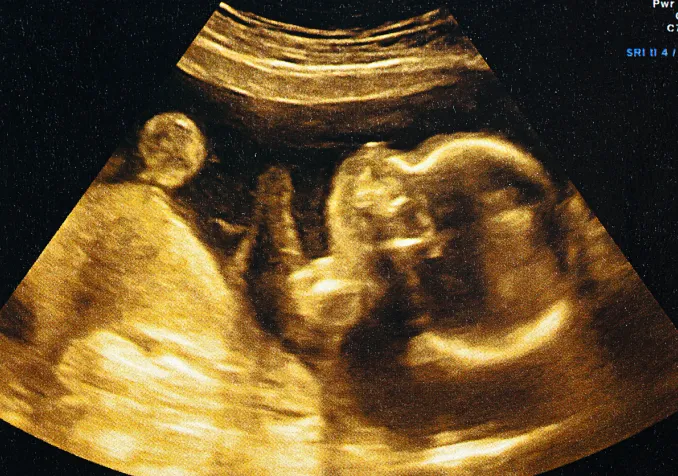

La Conférence Femmes des réformés suisses s’est tenue le 25 octobre sur le thème de «l’autonomie reproductive», entre PMA, GPA et coparentalité. Une journée qui a laissé place à plus de désaccords que de consensus.